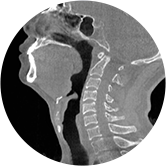

气道

颈椎